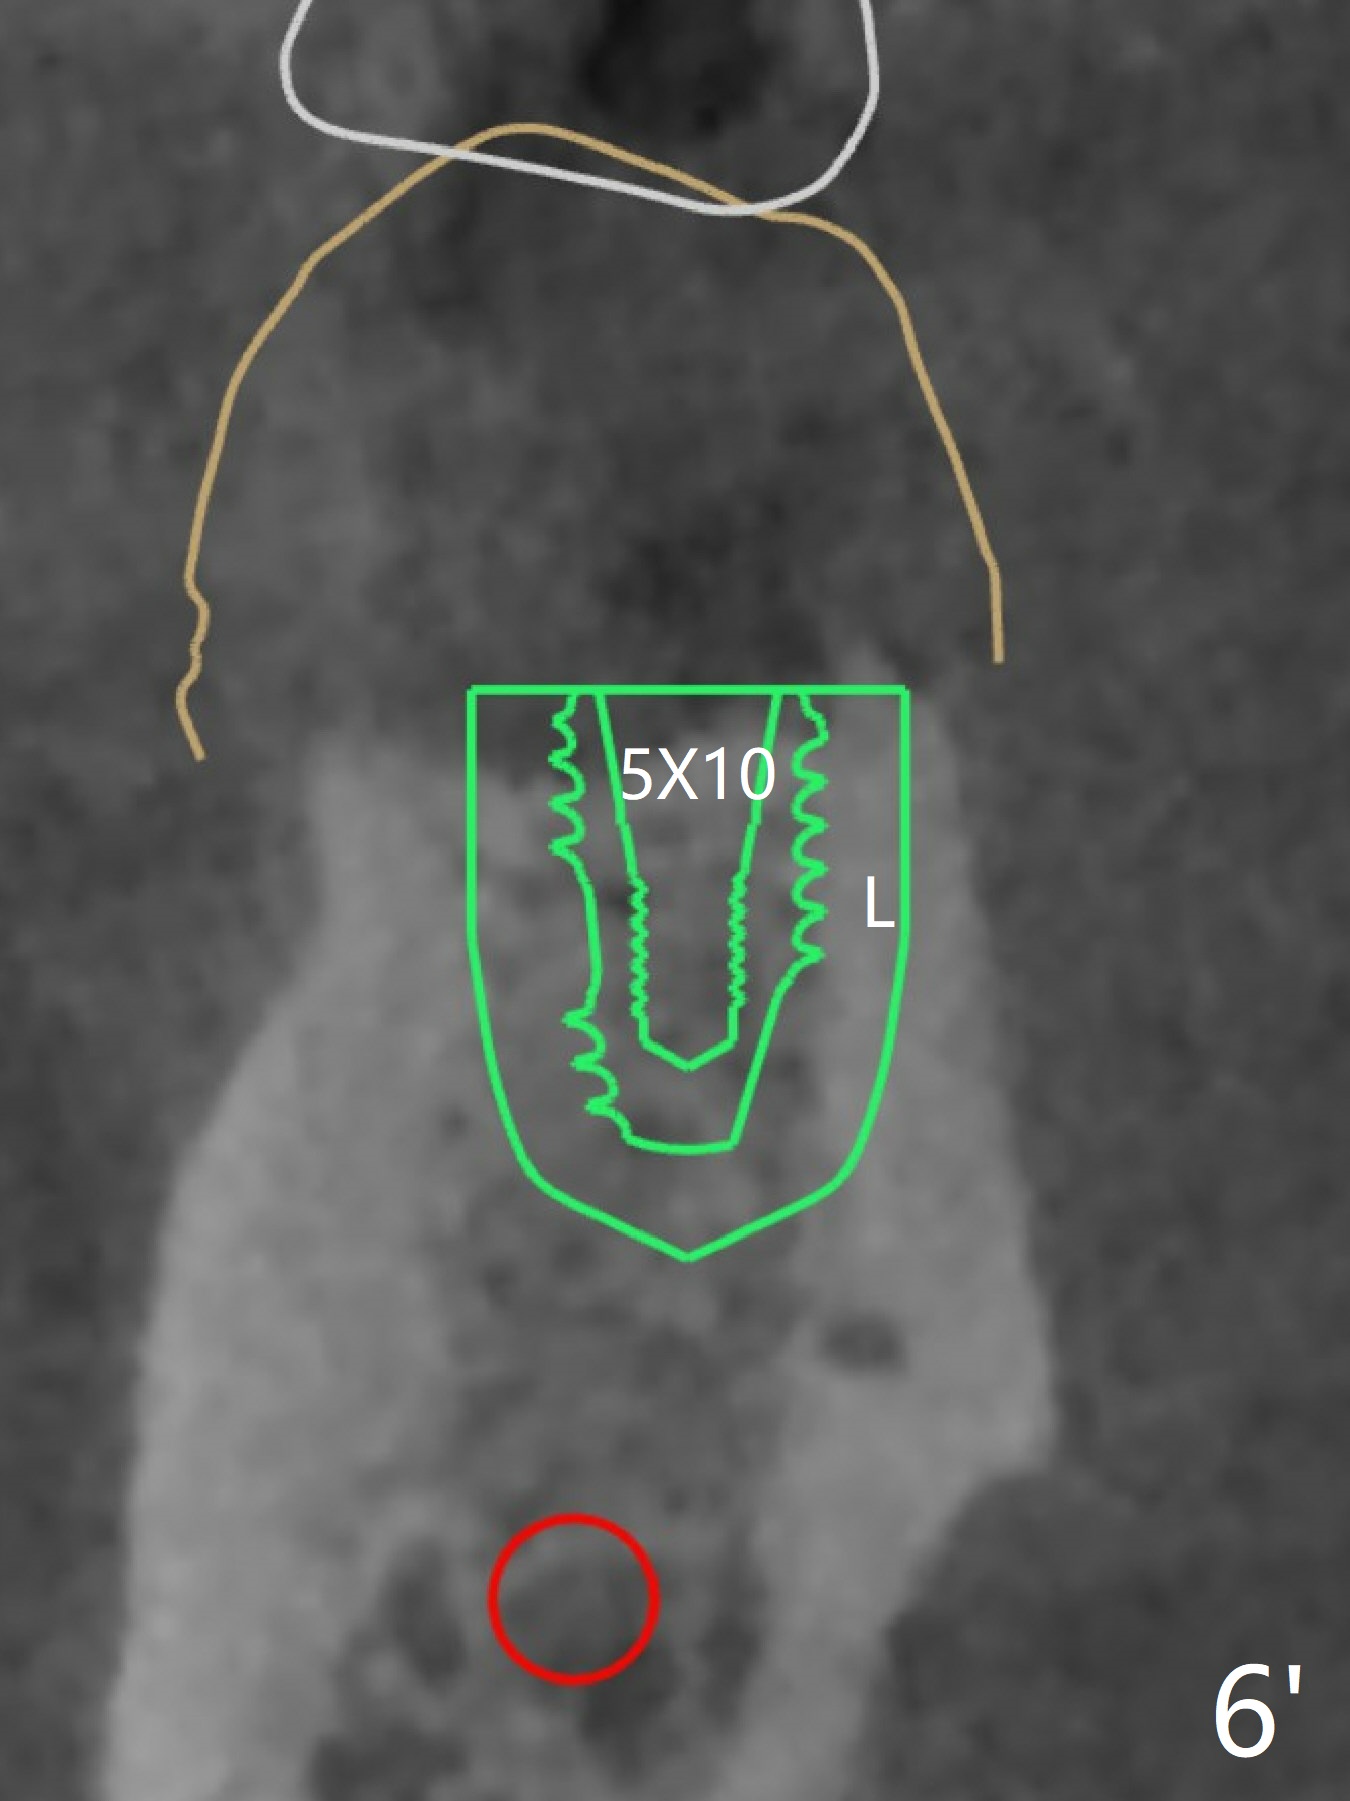

In spite of smoking reduction (1ppwk), the infection at #19, including buccal fistula (Fig.1 <) seems to be so severe that it affects pain threshold. Local anesthetics have to be added, including Bupivacaine IANB. When 4x10 mm drill is being applied, the patient feels pain. The plan is to use 4x11.5 mm drill as a final one. A 4x9 mm dummy implant is placed with 2.8 mm implant exposed (Fig.2 >), but it is subcrestal mesiodistally. Primary stability of a definitive 4.5x9 mm implant is satisfactory (Fig.3), but after initial bone graft, a 5x5.7(4) mm abutment is unable to be seated completely (<). Following 4.6 and 5.6 mm bone profile drills, the abutment remains incompletely seated (Fig.4). After fine turning, the abutment is fully seated; final round of bone graft (sticky bone) is placed mesiodistally (Fig.5 *) and buccolingually (Fig.6,7). It appears that there is tight fit between IBS implant and abutment. It is hoped that the excess bone graft with PRF is able to cover the coronal portion of the implant. If not, socket preservation should be done in this situation. In fact the implant is not placed lingual enough as compared to the design (Fig.6'). A 4.5 mm cortical drill should be used in a crown down fashion. In fact there is bone coverage coronally 5 months postop (Fig.8). Return to Prevent Molar Periimplantitis (Protocols, Table) No Deviation 12/14 Xin Wei, DDS, PhD, MS 1st edition 02/11/2020, last revision 06/30/2020